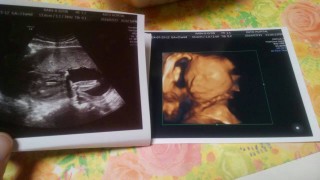

前回のエコーで、顔を腕で覆って見せてくれなかったので、今日はお顔見せてね♡ってエコー前にお腹をさすりながら言ってみたら、バッチリ正面で笑顔?も見せてくれました! 大きさは450g。羊水の量も平均的で赤ちゃんは大丈夫だけど、私自身に浮腫みが出てきたので、塩分控えましょうと言われてしまった。元気に産んであげるために、食事管理頑張ります!

6ヶ月検診時にもらったエコーです。

性別はまだわからなかったですが

こちらを向いてニコッと笑ってくれています☆

写真には右手がちょこんと乗っています。

なんだかアゴがでているのか?

そしたら旦那に似ていて嬉しいです☆

体重337グラム